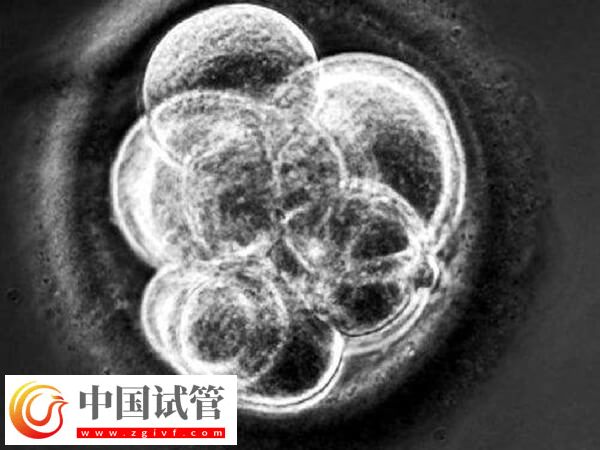

胚胎因素

優(yōu)質(zhì)胚胎在試管移植之后,染色體發(fā)生異變、遺傳物質(zhì)提讓改變等也會導(dǎo)致三代試管胚胎不著床;